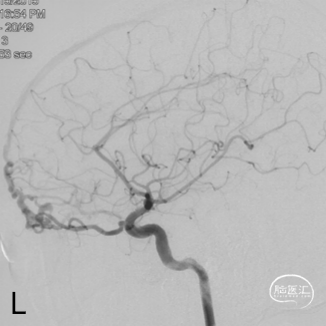

术前造影

双侧颈内动脉正侧位造影见前颅窝底硬脑膜动静脉瘘,双侧筛前动脉、筛后动脉向瘘口供血,通过皮层静脉向上矢状窦引流。

双侧颈外动脉正侧位造影见镰前动脉向瘘口供血。

左侧椎动脉正侧位造影未见明显异常。